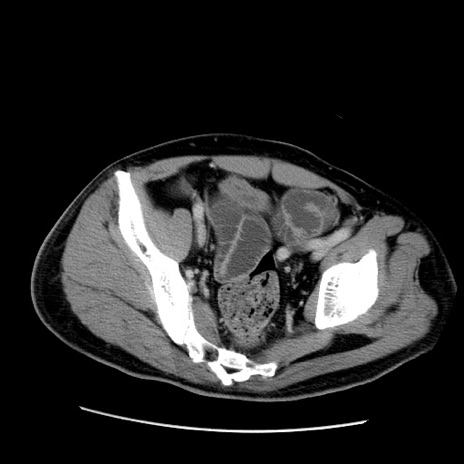

症例22(横断像)

【症例】50歳代男性

【主訴】腹痛

【現病歴】AVMからの被殻出血のため回復期リハ病棟入院中。 本日午後3時頃急に下腹部痛が出現した。

【既往歴】AVM、被殻出血、虫垂炎、高血圧

【身体所見】意識晴明、左半身不全麻痺、会話の理解は良好、36.5°C、腹部:膨隆、全体に板状硬、下腹部正中に圧痛点あり、反跳痛-、筋性防御不明、右下腹部にope scar

【データ】WBC 9400、CRP 0.06